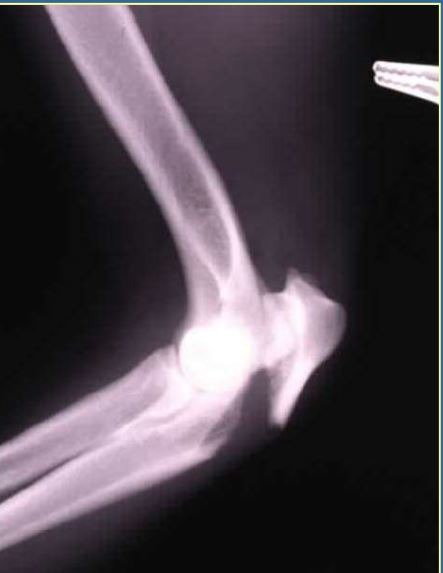

Salter Harris Type 2

Olecranon avulsion

Fx score WITHOUT luxation = 7-9

Fx score = 5-7

Repair: Tension band